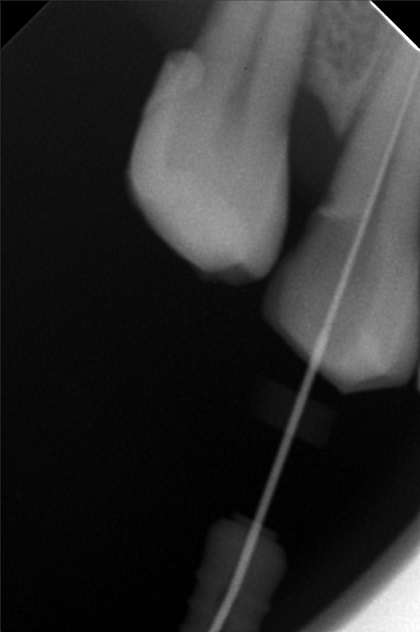

Edit Record Check our patient data records. Add patient information Patient Info Profile picture Last Name First Name Middle Name Birthdate Age Street Barangay City Country Zip Code Contact number Email Procedure 3/22/22- OP Lc 13 m/ 21 d/ 22 m/ 47 o/ b/ cervical xray 14 for rct 10/11/22 - OP (L); ACCESS #14, SCOUT #10 BL 18mm, EUGENOL. 10/14/22- 12/11/21/22- TF emax veneers 10/19/22 - 19mm, close w/ pulp devitalizer 09/02/23- op ** For change of crowns posterior Lower for Crown #15 08/13/24 OP 01/23/26 Alumina crwon #14 temporary crown OP Scanning File bangaros.jpg File 2 bongaros.jpg File 3 bongaros_02.jpg File 4 bongaros_03.jpg File 5 bongaros_04.jpg File 6 309497615_1081002115924778_349479569281481267_n.jpg File 7 bongaros_1.jpg File 8 bongaros_02_1.jpg File 9 File 10 File 11 File 12 File 13 File 14 File 15 File 16 File 17 File 18 File 19 File 20 Retain Record Retain Record Yes No Save Your Changes